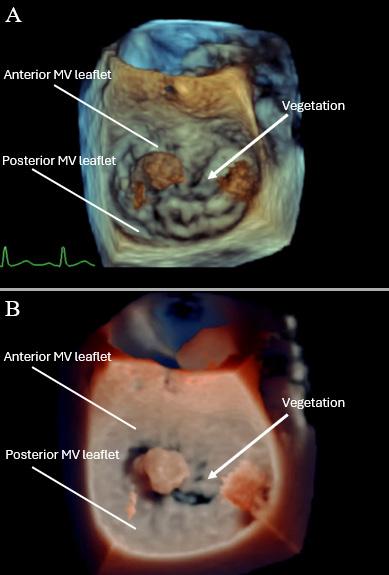

Hyaline casts Too numerous to count 0-2/hpf

329 Case Report: Early Valvular Repair of Rothia mucilaginosa Endocarditis with Intraparenchymal Hemorrhage from Septic Emboli

E Alley, K Holecko